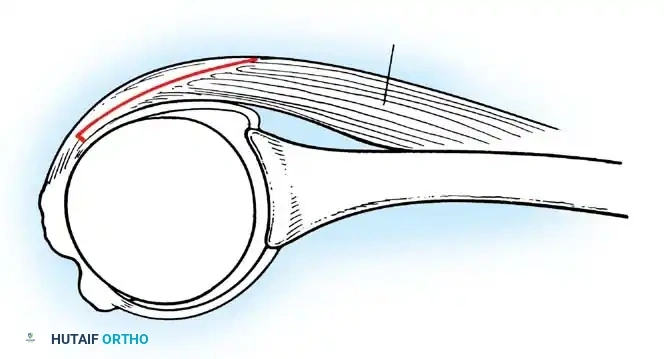

The Glenoid Labrum and Biceps Anchor

According to seminal studies by Howell et al., the effective depth of the glenoid is increased by 50% due to the presence of the fibrocartilaginous glenoid labrum. This structure acts as a bumper, increasing the humeral contact area to 75%. Integral to the superior glenoid labrum is the insertion of the long head of the biceps tendon, which blends indistinguishably into the posterior and anterior superior labrum. Matsen et al. conceptualized the labrum as a "chock block" that prevents excessive humeral head translation and rollback during physiological loading.

The shoulder joint capsule is inherently lax and thin, offering little resistance in isolation. However, it is reinforced anteriorly by three distinct capsular thickenings—the glenohumeral ligaments—which fuse intimately with the labral attachment on the glenoid rim. Turkel et al., alongside O’Brien, Warren, and Schwartz, have extensively mapped these structures.

- Inferior Glenohumeral Ligament (IGHL) Complex: The most critical static stabilizer. It attaches to the glenoid margin from the 2-o’clock to 3-o’clock positions anteriorly, extending to the 8-o’clock to 9-o’clock positions posteriorly. Its humeral attachment lies below the articular margin on the anatomical and surgical neck. O’Brien et al. described this complex as a "hammock-like" structure consisting of a thickened anterior band, a posterior band, and a thinner axillary pouch.